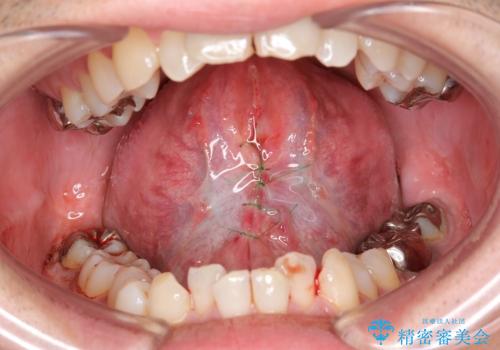

【舌小帯切除】ら行が言いづらい

- 滑舌が気になり来院されました。

舌小帯を形成することにより、滑舌の改善を図ります。

舌小帯形成では舌の可動域拡大や滑舌の改善を行うことが出来ます。

また、当日に処置が可能です。